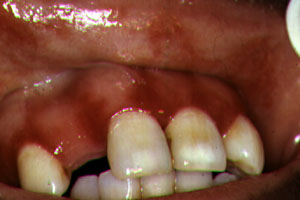

de la boca y organismos ocasionalmente atípicos como

pseudomonas, se han aislado bacilos entéricos y bacterias que no

pertenecen a la flora oral..

Ocasionalmente otras bacterias pueden presentar ulceración oral

como el mycobacterium avium intracellularae, mycobacterium

tuberculosis, E.coli, actinomyces, Klebsiella y pseudomonas.

Se ha descrito en un número pequeño de casos, Angiomatosis bacilar

oral causado por Rochalimaea henselae. |